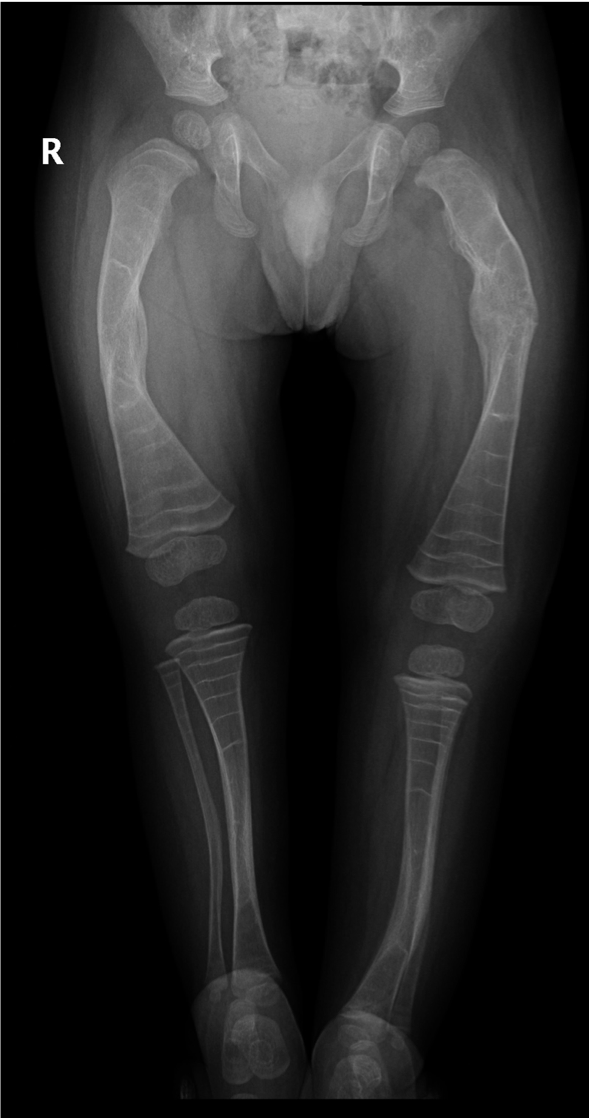

A mother brought her six-week old daughter to the ED. The child had become very irritable after the mother had accidentally twisted the infant’s right leg whilst changing her nappy.

The child was irritable and became distressed when her right leg was examined.

What abnormalities can you see in the X-ray of this child’s lower limb bones?

Can you explain the abnormal appearance?